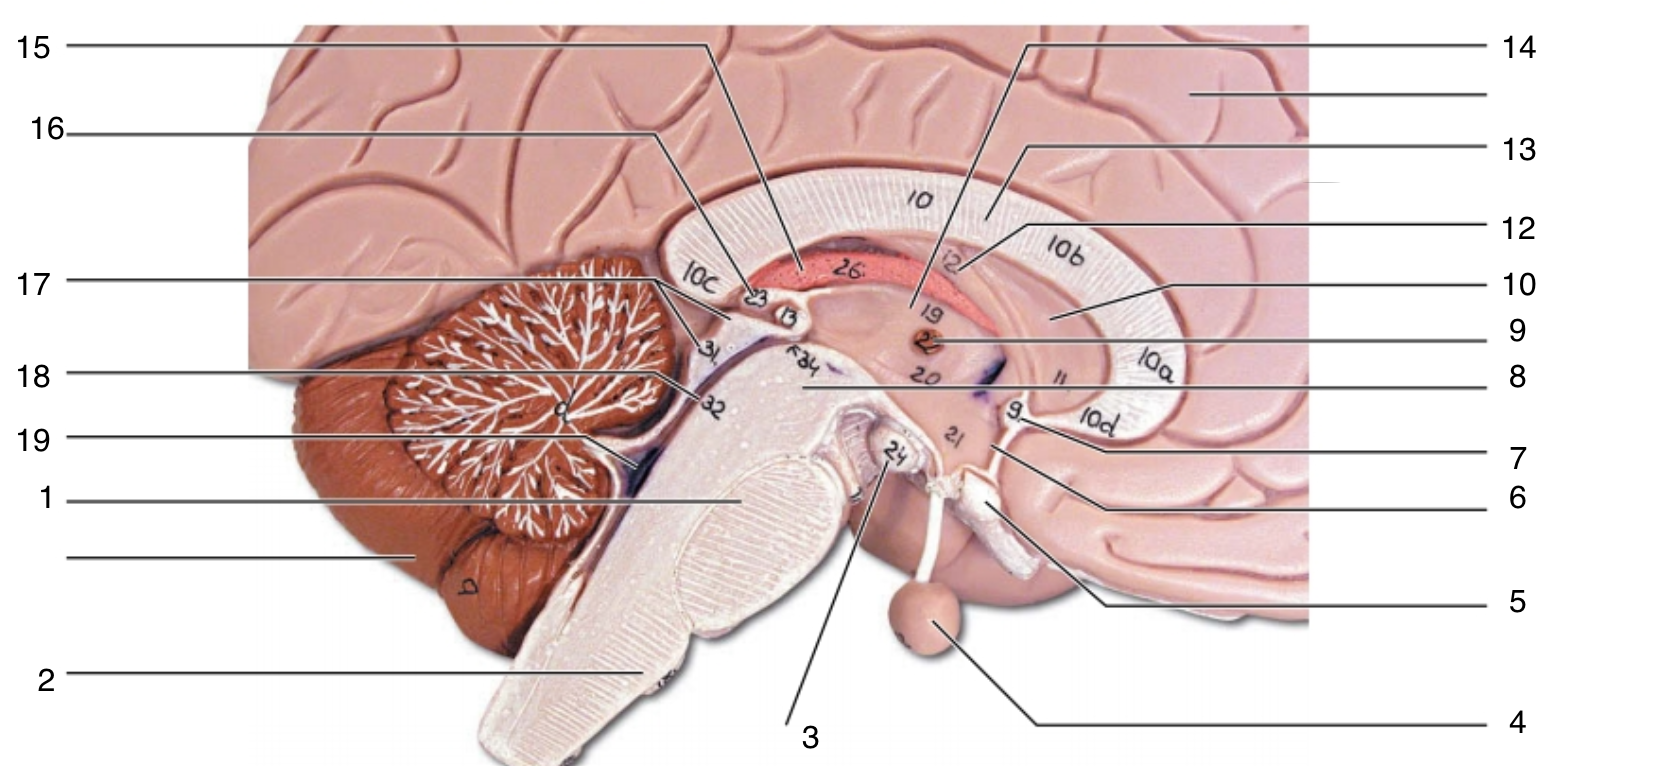

Brain Stem

1

pons

1

2

medulla oblongata

2

3

mammillary body

3

4

pituitary gland

4

5

optic chiasma

5

6

hypothalamus

6

7

anterior commissure

7

8

midbrain

8

9

interthalamic adhesion

9

10

septum pellucidum

10